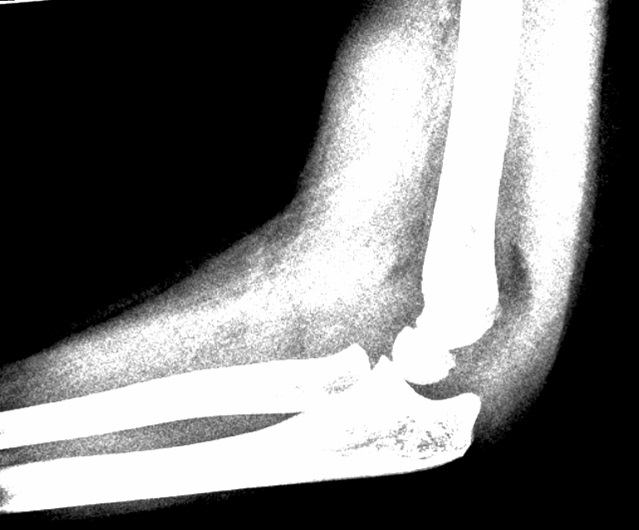

Rtg:

Se efter ”fad pad sign” som udtryk for ledansamling.

Manglende ansamling udelukker ikke fraktur.